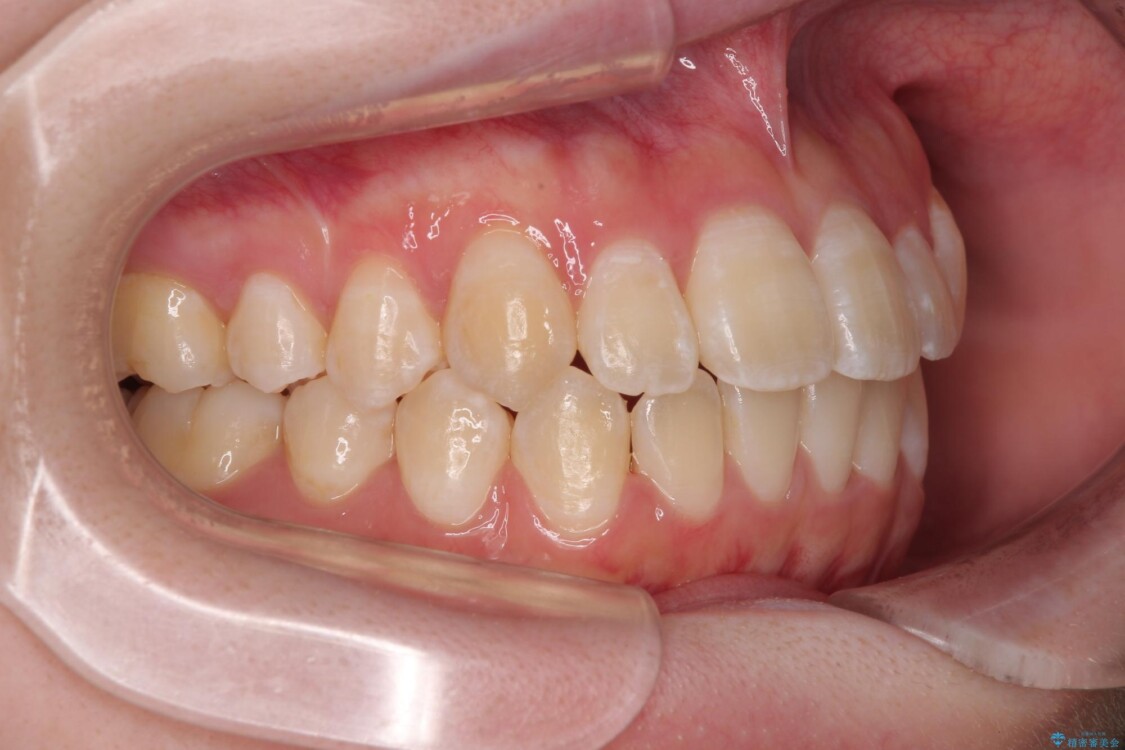

患者様の協力もあり、およそ1年間で治療を完了。スムーズな歯の移動を実現しました。

上下の正中(真ん中のライン)もずれることなく、バランスの取れた美しい歯並びに。笑顔に自信を持てる仕上がりとなりました。

治療後

• 【モニター】前歯のデコボコをスッキリ解消!目立ちにくいワイヤー矯正でスピーディに治療完了 治療後画像